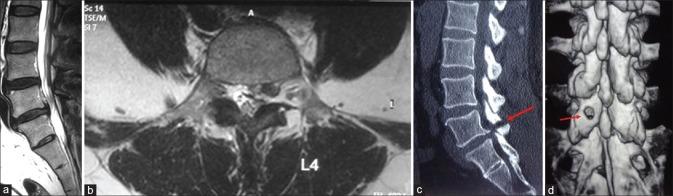

The study period extended from January 2008 to December 2014. All patients with lumbar herniated discs who failed conservative management were selected for surgery and underwent routine erect radiographs and magnetic resonance imaging (MRI) of the lumbar spine. The patients with cranially or caudally migrated discs were included in this study. The technique involves approaching migrated disc through an oval window (sculpted through an 18 mm tubular retractor using a burr) in the lamina precisely over the location of the migrated disc as predicted by the preoperative MRI (inferior lamina for inferior migration and superior lamina for superior migration). The perioperative parameters studied were operative time, blood loss, complications, Oswestry Disability Index (ODI), and visual analog scale (VAS) for leg pain before surgery and at last followup. In the study, 4 patients underwent a postoperative computed tomography-scan with a three-dimensional reconstruction to visualize the oval window and to rule out any pars fracture. All technical difficulties and complications were analyzed.

研究时间从2008年1月至2014年12月。所有经保守治疗无效的腰椎间盘突出症患者均入选接受手术,并进行腰椎的常规站立位X线片和磁共振成像(MRI)检查。纳入向上或向下移位椎间盘的患者。该技术包括通过术前MRI预测的移位椎间盘位置上方椎板上的椭圆形窗口(使用磨钻通过18mm管状牵开器钻出)接近移位的椎间盘(向下移位时为下位椎板,向上移位时为上位椎板)。研究的围手术期参数包括手术时间、失血量、并发症、Oswestry功能障碍指数(ODI)以及术前和末次随访时的腿痛视觉模拟评分(VAS)。在本研究中,4例患者术后接受了计算机断层扫描三维重建,以观察椭圆形窗口并排除任何椎弓根骨折。分析了所有技术难点和并发症。